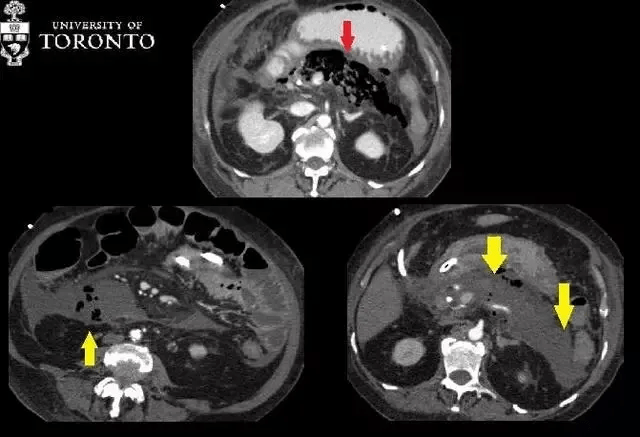

该患者被送入重症监护室 , 并给予高剂量抗生素静脉滴注 。 之后患者病情稳定 , 未进行手术治疗 。 两个星期后 , 患者白细胞计数升高 , 再次昏厥 。 入院当天的 CT 扫描显示广泛的胰腺坏死 。 胰腺组织几乎完全由气泡(红色箭头)所取代 。

诊断:患者被确诊为急性坏死性胰腺炎 , 且可能合并感染 。

【治疗|精选病例:典型的急性坏死性胰腺炎】治疗:患者静脉用抗生素治疗了两个星期 , 之后患者出现了大量的混合性腹水 , 胰床上见 aeric 脓肿 , 位于钩突下方右侧可见另一个腹膜后脓肿(黄色箭头) 。